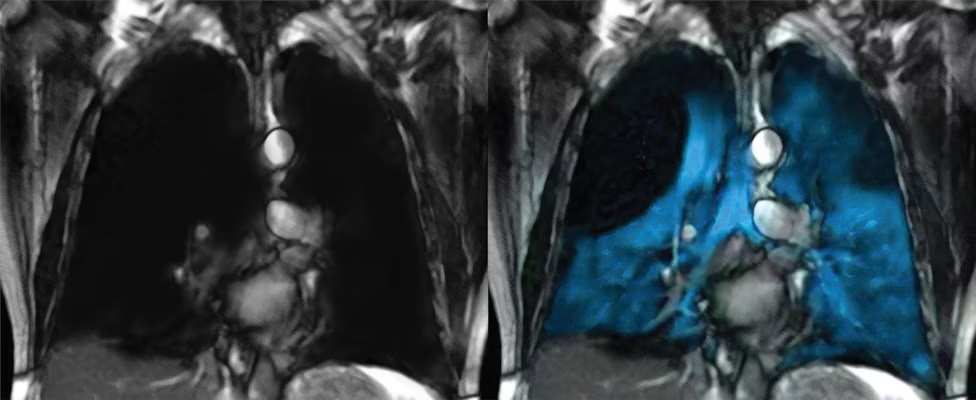

Polarean’s GEHC-compatible Xenoview 3T chest coil is a flexible, single-channel, transmit-receive radiofrequency coil for imaging xenon-129 nuclei. This is done while a patient is positioned inside a GEHC Signa Premier 3T or Discovery MR750 3T MRI scanner equipped with the latter's multinuclear spectroscopy capability.

The coil is to be used in conjunction with hyperpolarized xenon-129 for oral inhalation for the evaluation of lung ventilation in adults and pediatric patients, aged 12 years and older. Polarean said the coil supports institutions with GEHC-compatible MRI systems looking to adopt xenon MRI.